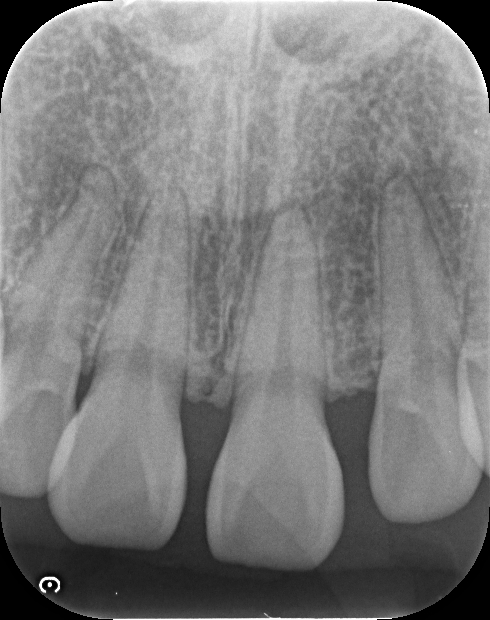

デンタルレントゲンで前歯の部分を確認します。虫歯も無く骨も健康的な状態が保たれていることから、デンタルIQの高い患者さんということがわかります。